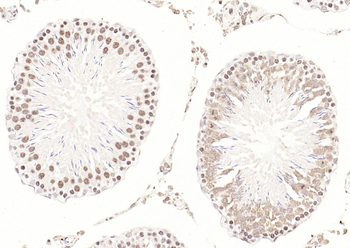

CDKN1A Antibody

Catalog Number: orb682382

| Description | CDKN1A Antibody |

| Target | CDKN1A |